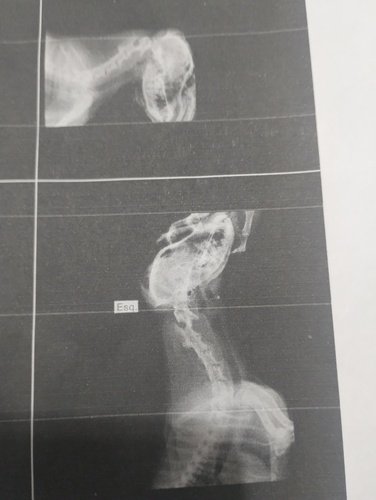

Há menos de um mês descobrimos um problema em sua coluna, com isto tendo fortes dores, no momento estão sendo controladas com medicação.

Agora precisamos de um neurologista, seguido uma ressonância e ver como iremos continuar o tratando ( até uma possível cirurgia, se caso for).